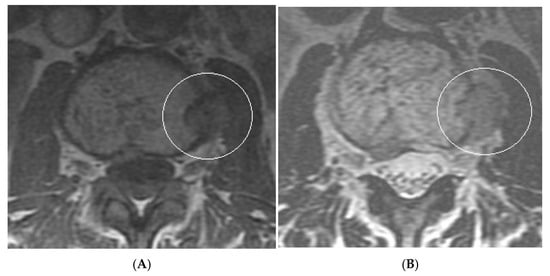

Figure 14.

Collision Lesions: Typical and atypical haemangioma of vertebral body. (A) Axial T1W MRI demonstrating a classic haemangioma with a T1 hyperintense lesion occupying the vertebral body, with a smaller atypical T1 hypointense lesion (circled) adjacent, in keeping with an atypical haemangioma. (B) Axial T2W MRI with the same lesions—the atypical lesion to the left side of the patient (vertebral body) has a higher vascular component and therefore is more hyperintense than the adjacent and larger typical haemangioma. The larger lesion still remains hyperintense on T2, in keeping with predominant internal fat content. (C) Sagittal T1W spine MRI. (D) Sagittal T2W spine MRI. (E) Sagittal STIR spine MRI demonstrating fat suppression within the typical haemangioma with hyperintense signal within the atypical haemangioma as a collision lesion example.

Figure 15.

Collision Lesions: Renal cell carcinoma metastases within a haemangioma of vertebral body, Case 1. (A) Axial T1W MRI—A large T1 hyperintense lesion with typical appearances of a haemangioma within the vertebral body, associated with a smaller peripheral located T1 isointense lesion with extraosseous component (circled). (B) Axial T2W MRI—Same case with T2 hyperintense vertebral body lesion confirming internal fat content and the eccentrically located T2 hyper- to isointense lesion proven to be a renal cell carcinoma on histology.

Figure 16.

Collision Lesions—Renal cell carcinoma metastases within a haemangioma of the vertebral body, Case 2. (A) Axial T1W MRI with a typical vertebral body haemangioma with an abnormal low T1 signal in its posterolateral aspect with periosteal change (circled). (B) Axial T2W MRI demonstrates the aggressive lesion within and adjacent to the typical haemangioma in image (A). (C) Sagittal STIR MRI—Fat-suppressed haemangioma with a hyperintense (biopsy-proven) metastases in its posterior aspect involving the pedicle.